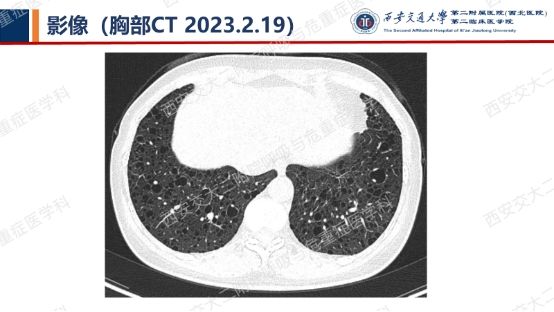

阅影探案,析病寻踪 // 第一期(上)

影像方寸藏玄机,同影异病辨真章。让我们一起抽丝剥茧,揭秘医学真相,解锁临床那些有意思的病例谜题吧!

结合以上患者病史及胸部CT,第一诊断分别考虑???欲知答案,且看后期!!!